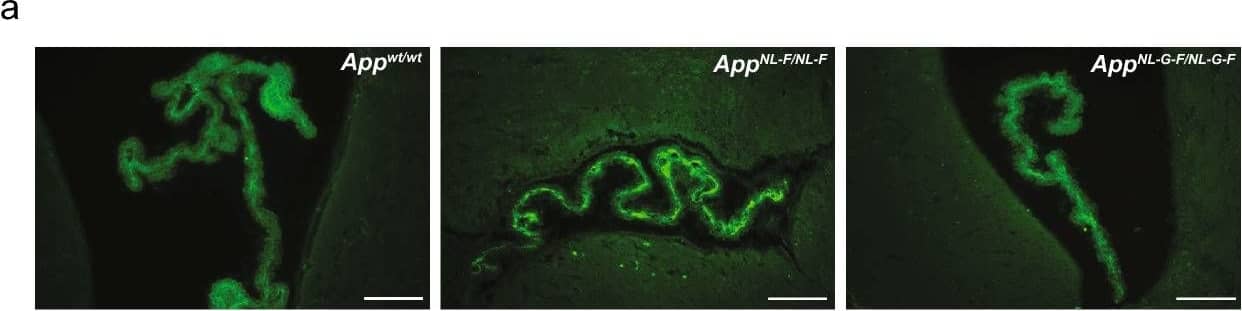

Detection of Mouse Decorin by Immunohistochemistry Increased CSF-decorin in three different mouse models of A beta pathology. a, b Immunostaining and quantification of decorin in the ChP. Scale bars, 100 µm. (n = 4). c Double immunostaining of DCN and PV or d SRIF in mouse hippocampus. e Quantification of decorin-positive cell-type distribution. Scale bars, 500 µm. (n = 3). f, g Immunostaining and quantification of decorin in the hippocampus. Scale bars, 500 µm. (n = 4). h Mouse CSF-decorin levels in three months old (n = 5), i 13 months old (n = 4–5), j 18 months old (n = 3–5) mice were measured by ELISA and quantified. k CSF-decorin levels in AppNL-F/NL-F mice of different ages were measured and quantified. (n = 3–5). l Decorin levels in A beta 42 treated mouse primary neurons and (m) were quantified (n = 4). n Quantification of decorin levels in conditioned media. (n = 8). Data in (b, g–k) were analyzed by one-way ANOVA followed by Dunnett’s multiple comparisons test. Data in (m, n) were analyzed by student’s t-test. Data in (e) were analyzed by two-way ANOVA followed by Tukey’s post hoc test. Data are represented as mean ± SEM; *p < 0.05, **p < 0.01, ***p < 0.001, ****p < 0.0001. DCN decorin, PV parvalbumin, SRIF somatotropin release-inhibiting factor, PN pyramidal neurons, ns not significant Image collected and cropped by CiteAb from the following open publication (https://pubmed.ncbi.nlm.nih.gov/35787306), licensed under a CC-BY license. Not internally tested by R&D Systems.